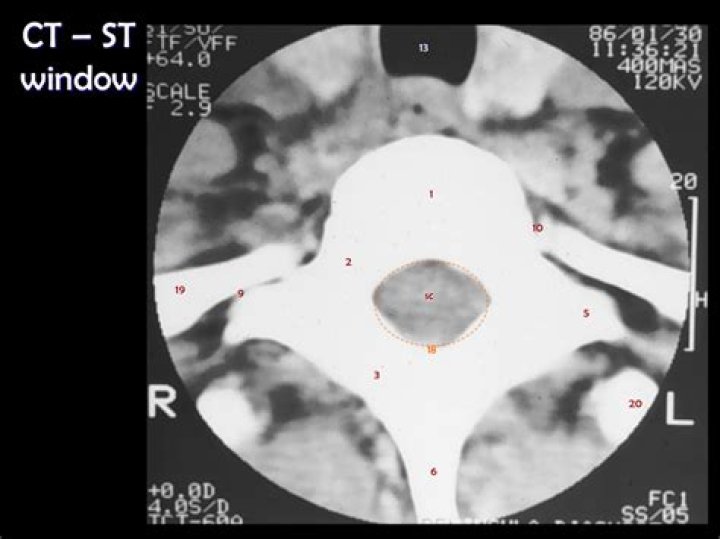

What is soft tissue window

A soft tissue window is used to view most organs. A soft tissue window cannot be used for lung parenchyma, as lung density (−500 HU) is outside range and will appear completely black.

Part 1 Figure 9. Common window settings used when interpreting a normal CT Brain scan. A: Brain window (WW 80, WL 40); B: Bone window (WW 3000, WL 500); C: Soft tissue window (WW 260, WL 80); D: Stroke window (WW 40, WL 40).